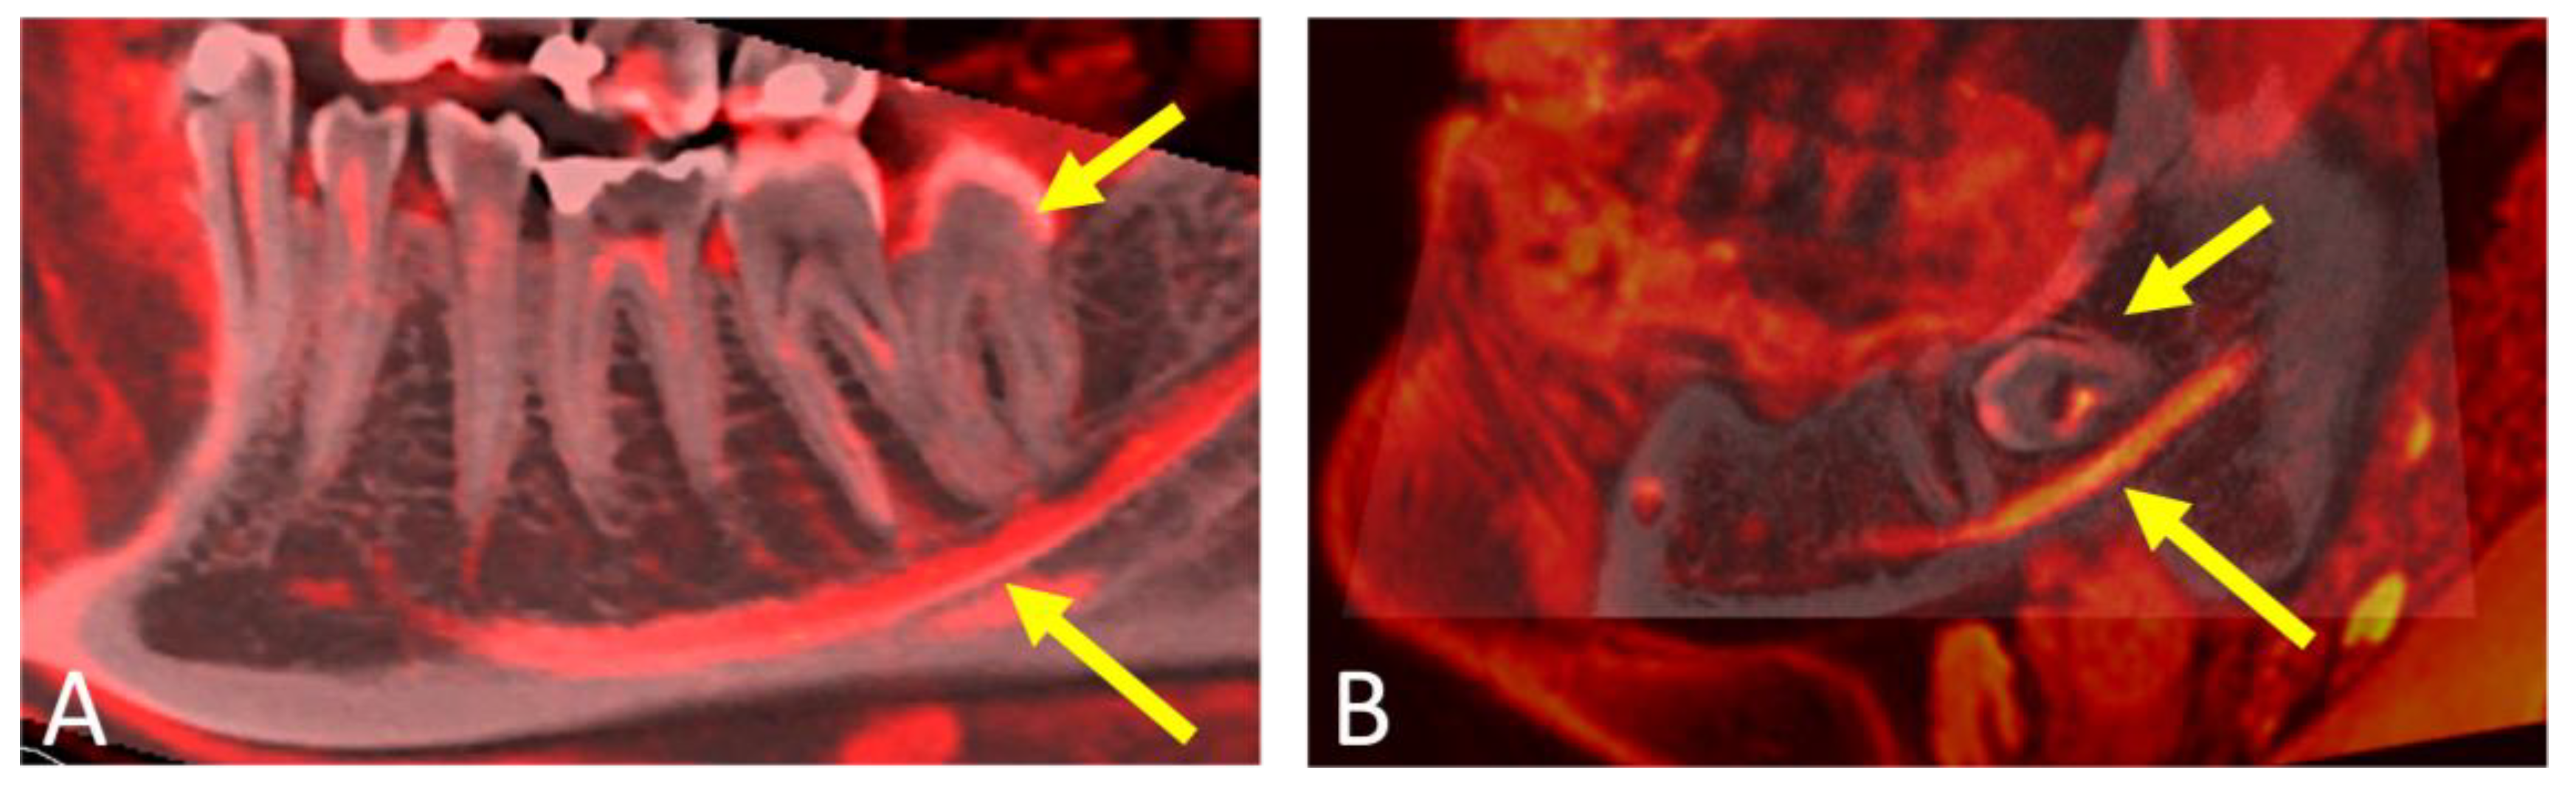

- Al-Haj Husain, A.; Solomons, M.; Stadlinger, B.; Pejicic, R.; Winklhofer, S.; Piccirelli, M.; Valdec, S. Visualization of the Inferior Alveolar Nerve and Lingual Nerve Using MRI in Oral and Maxillofacial Surgery: A Systematic Review. Diagnostics 2021, 11, 1657. [Google Scholar] [CrossRef] [PubMed]

- Al-Haj Husain, A.; Stadlinger, B.; Winklhofer, S.; Müller, M.; Piccirelli, M.; Valdec, S. Mandibular Third Molar Surgery: Intraosseous Localization of the Inferior Alveolar Nerve Using 3D Double-Echo Steady-State MRI (3D-DESS). Diagnostics 2021, 11, 1245. [Google Scholar] [CrossRef] [PubMed]

- Al-Haj Husain, A.; Valdec, S.; Stadlinger, B.; Rucker, M.; Piccirelli, M.; Winklhofer, S. Preoperative visualization of the lingual nerve by 3D double-echo steady-state MRI in surgical third molar extraction treatment. Clin. Oral Investig. 2022, 26, 2043–2053. [Google Scholar] [CrossRef]